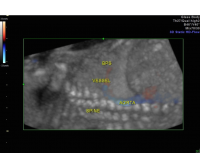

Bronchopulmonary sequestration coronal 3D